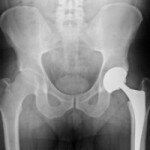

This happened two years after the Dartmouth resident got an implant on his left hip at the Queen Elizabeth II Hospital in Halifax. Ideally, a hip implant should last around 10 to 15 years.

The next day he was transferred to the QE II hospital and got a revision surgery to correct the broken neck of the implant. His doctor who performed the surgery told him the broken device was a faulty product.

However, the story doesn’t end there. It turns out the second surgery didn’t go well either – the device was loose, and the stem and Taylor’s femur bone didn’t adjust well so less than half a year later he had to undergo a third operation.

He says lawsuits on hip implant failures have been on the rise in recent years following medical device companies started making the metal-on-metal model, Wright’s Profemur products is one example. The medal parts rub against each other and release toxic particles in the patients’ body and the parts themselves gets fragile and become easier to break. Studies by medical journal Lancet suggest a higher failure rate of metal-on-metal models compared to metal-on-ceramic or metal-on-plastic models.